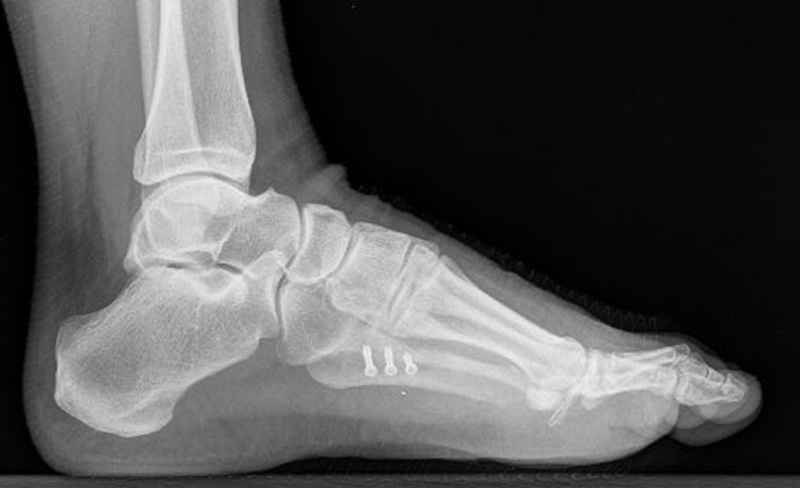

Abb. 12a: Typ III Deformität präoperativ im belasteten dp Röntgenbild.

Abb. 12b: Dorsoplantare Röntgenkontrolle nach medial schließender Osteotomie mit Schraubenosteosynthese.

Abb. 12c: Schrägaufnahme nach medial schließender Osteotomie mit Schraubenosteosynthese.

Abb. 12d: Seitliche Aufnahme nach medial schließender Osteotomie mit Schraubenosteosynthese.